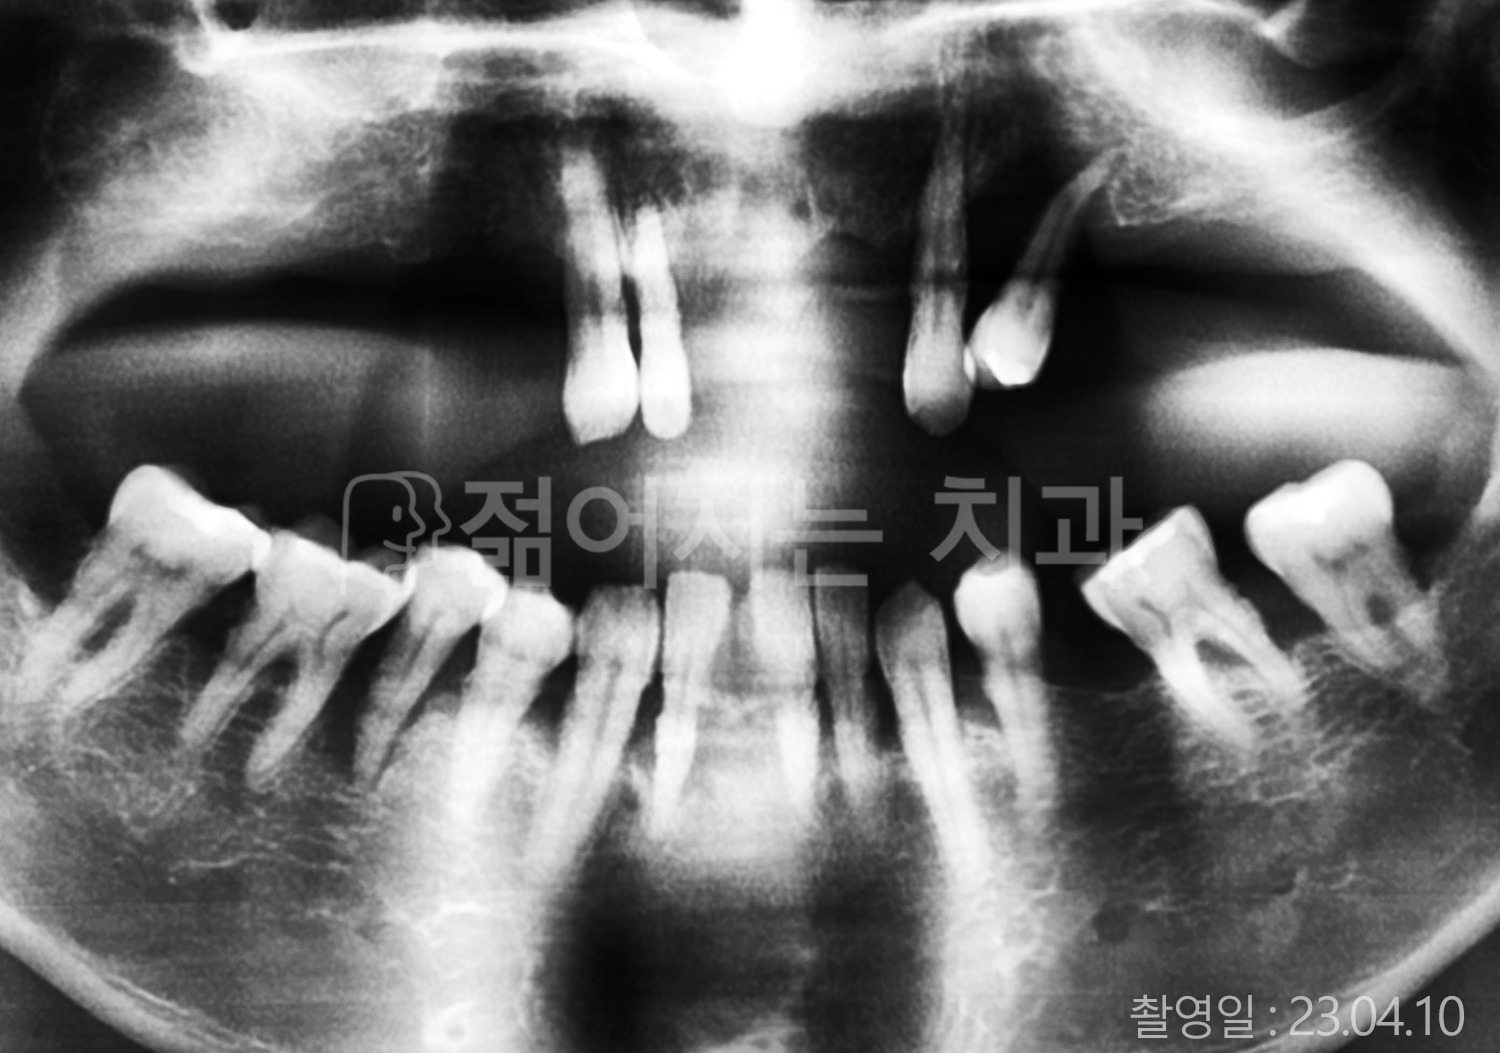

• 40대 전체치아 10개 이상 임플란트

• 70대 당뇨 전체치아 10개 이상 임플란트

• 60대 전체치아 10개 이상 임플란트

• 60대 고혈압, 당뇨, 고지혈증 전체치아 10개 이상 임플란트

• 50대 전체치아 10개 이상 임플란트

• 70대 고혈압, 당뇨 전체치아 10개 이상 임플란트

• 60대 고혈압 전체치아 10개 이상 임플란트

• 50대 고혈압, 당뇨, 고지혈증 전체치아 10개 이상 임플란트

• 60대 고혈압, 고지혈증 전체치아 10개 이상 임플란트